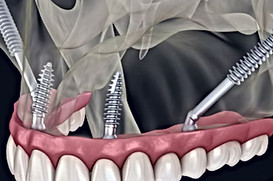

Zygomatic implants are a game-changer for patients with severe bone loss, but mastering this advanced technique requires specialized training. With so many courses available globally, choosing the right one can be challenging.